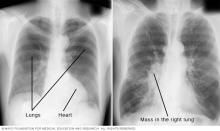

Medical image of chest X-rays

A chest X-ray helps detect problems with the heart and lungs. The chest X-ray on the left is typical. The image on the right shows a mass in the right lung.